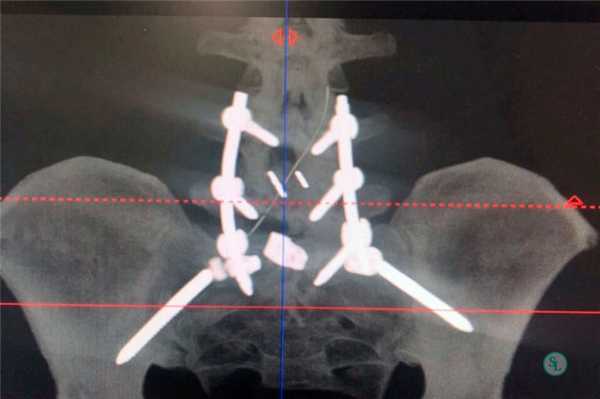

Чтобы иммобилизация позвоночно-двигательного сегмента была максимально надежной, нередко операция дополняется выполнением транспедикулярной фиксации. В таком случае устанавливаются специальные металлические конструкции, которые еще более упрочняют скрепление тел позвонков.